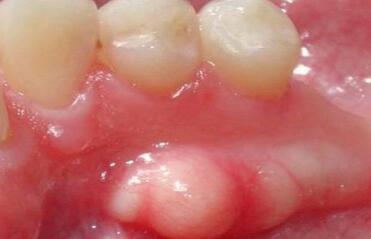

Egzostoza kości szczęki to łagodny guzek, który objawia się w postaci wyrostka kostno-chrzęstnego (osteofit), który tworzy się na powierzchni kości. Egzostoza to określenie guzów i narośli kostnych, które tworzą się na jej powierzchni. Osteofity to zmiany określane, jako dzioby lub narośla kostne, których cechą charakterystyczną jest miejscowa dobudowa tkanki kostnej. Guzy mają charakter zarówno pojedynczy, jak i wielokrotny i mogą być rozmieszczone w różnych częściach tkanki kostnej, w tym w kościach szczęki. Należy zauważyć, że w przeważającej większości przypadków osteofity szczęki znajdują się na zewnętrznej (policzkowej) powierzchni wyrostka zębodołowego, a osteofity żuchwy zlokalizowane są po wewnętrznej (językowej) stronie. Nieco rzadziej występuje wał podniebienny, który jest wyrostkiem w okolicy szwu podniebiennego pośrodkowego.

Pacjent z egzostozą kości szczęki swobodnie otwiera żuchwę i nie skarży się na dyskomfort. Błona śluzowa nad osteofitem ma zwykle bladoróżowy kolor. Zwykle nie ma zmian chorobotwórczych, błona śluzowa pozostaje ruchoma.

Egzostozy kości szczęk pojawiają się w postaci wypukłego wyrostka, guzka, narośli, które pojawił się bez wyraźnego powodu.